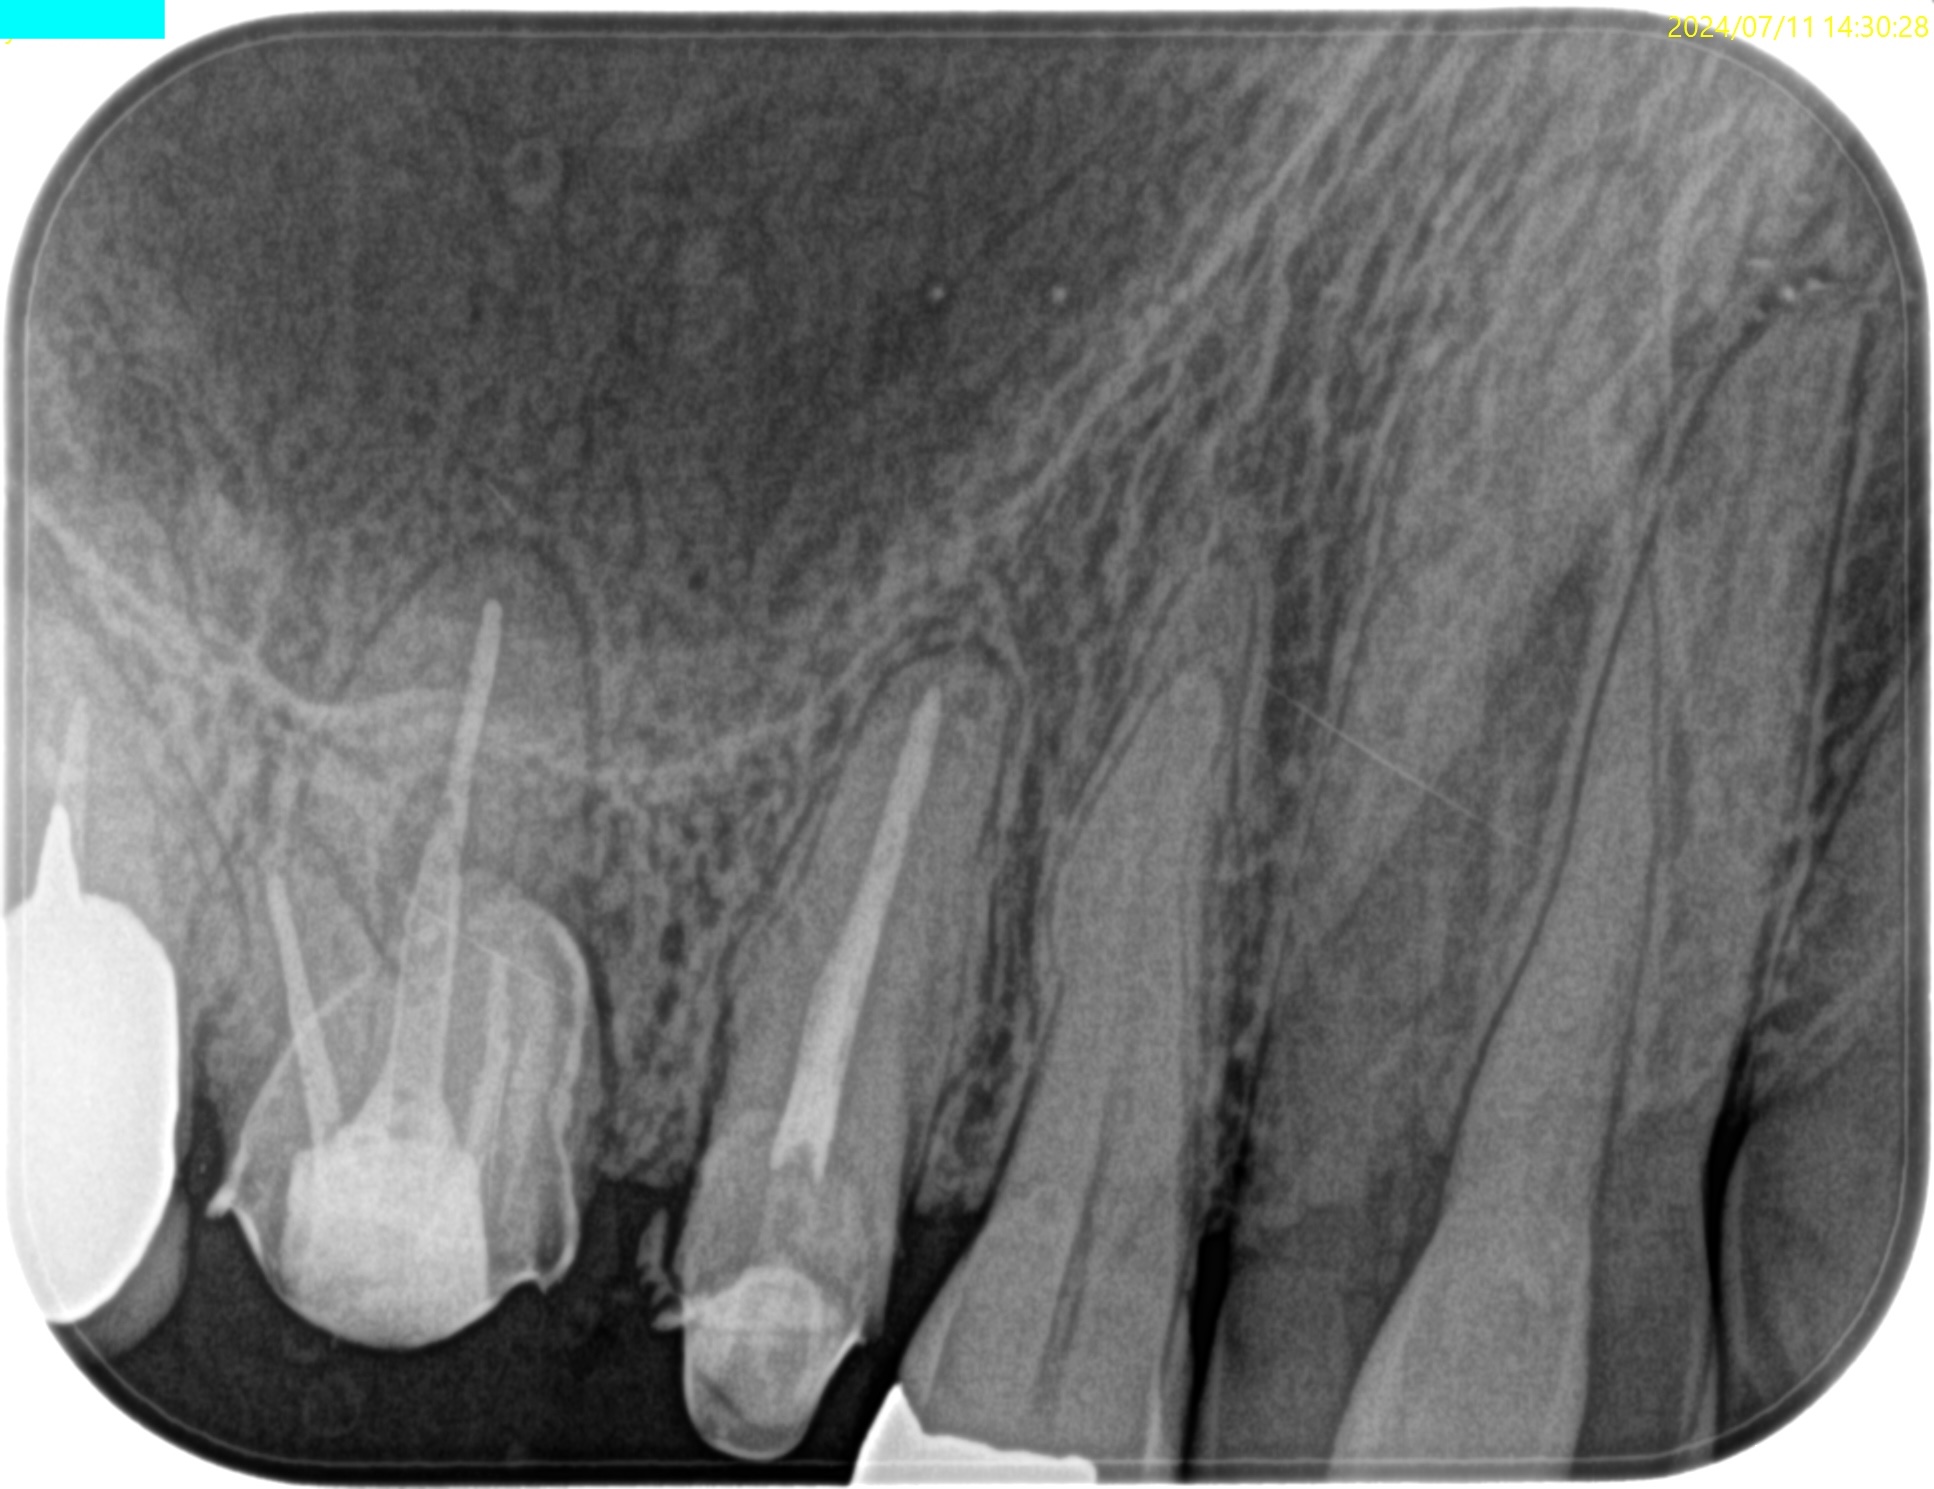

#3 MB Apicoectomy(2024.7.11)

術後にPA, CBCTを撮影した。

問題はないと思われる。

縫合して終了した。